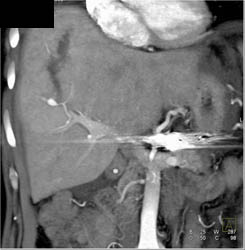

Cholangiocarcinoma